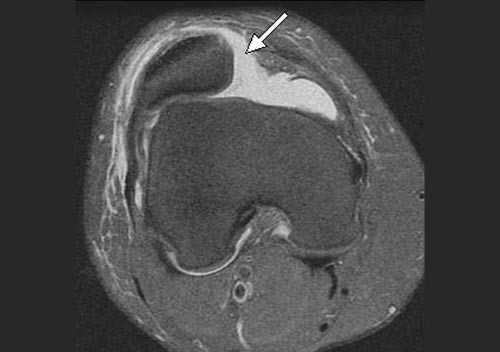

в) Магнитно-резонансная томография (МРТ) является наиболее информативным методом, позволяющим обнаружить участки отека костного мозга, локализовать разрыв МБНС, диагностировать хондральные повреждения, сопутствующие повреждения менисков и связок коленного сустава:

• На аксиальной МР-томограмме (рис. 6) видны признаки отрыва МБНС в области ее прикрепления к бедренной кости.